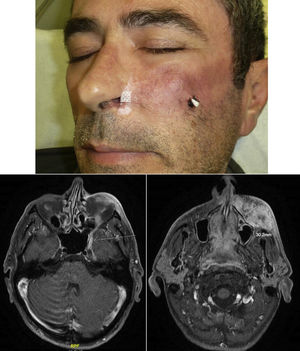

When there are symptoms such as pain, paresthesia, anesthesia, or paralysis and/or radiological evidence of spread of PNI, it is classed as clinical PNI22,23 (Figure 1). The initial symptoms are usually very subtle, with a tingling or numb sensation; these could go unnoticed if the physician does not have a high suspicion of PNI.24 The absence of abnormalities in imaging tests performed on patients with clinical PNI further hampers management.25,26 Pain and motor deficit may be seen in more advanced cases (Figure 2).

RadiologyMagnetic resonance is the most sensitive imaging technique for diagnosis of PNI.32,45–47 The study of the whole nerve tract makes it possible to evaluate the presence and extension of PNI in patients who present with signs or symptoms of neurological involvement and thus to plan therapy. The primary findings48 are uptake of the whole circumference of the nerve in gadolinium-enhanced T1-weighted sequences, increase in the normal diameter of the nerve, and obliteration of juxta-foraminal fat pads (Fig. 3).